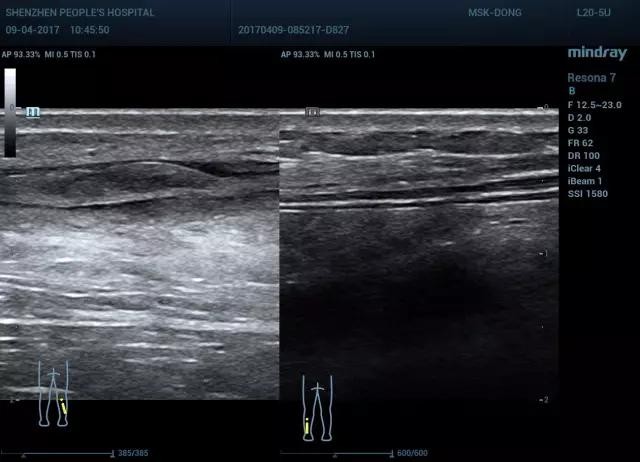

图8 双侧对比(图右 部分撕裂,图左 正常)